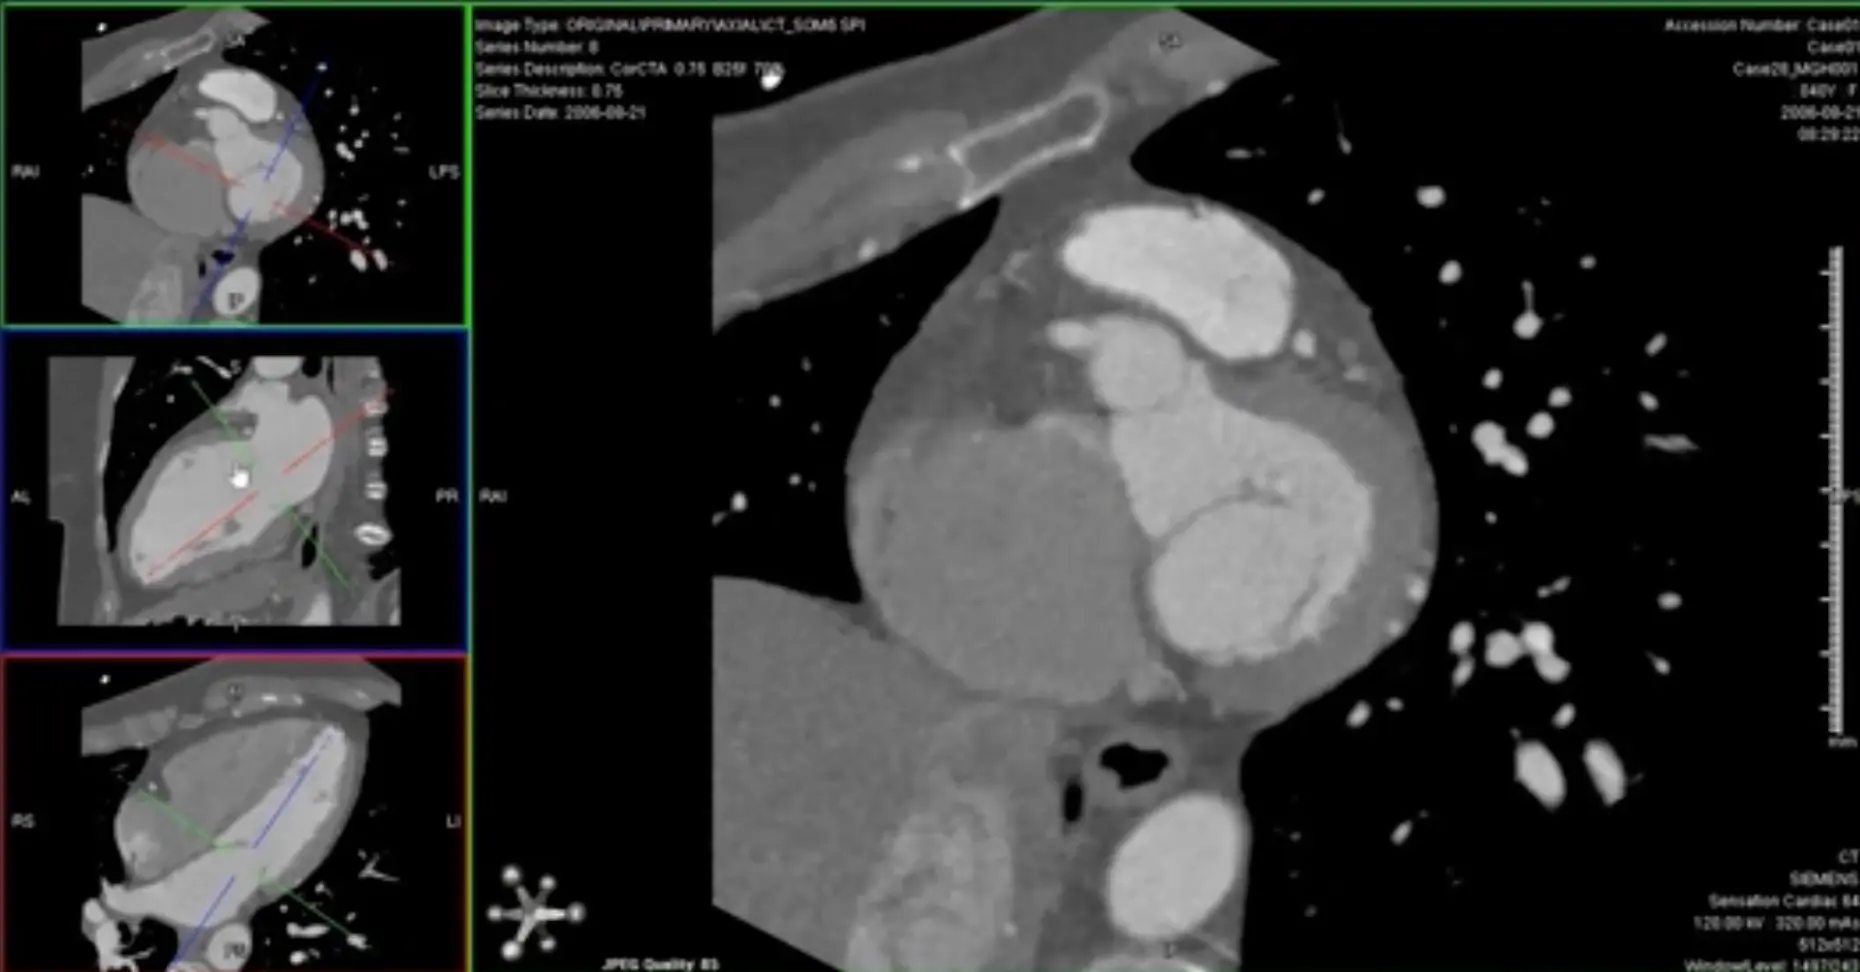

- Switch to MIP view

- MIP will help give you an overview of the vessel. Once you identify some areas of concern → switch to thin-slice images for closer investigation 🔍 and evaluation for stenosis.

- Go down to the thinnest possible section within the MIP view

Avoid assessing diameter stenosis using thick-slab MIP

When quantifying stenosis, you will always want to use thin slice images.

MPR of ‘C’ view of RCA

Above, but changed to MIP